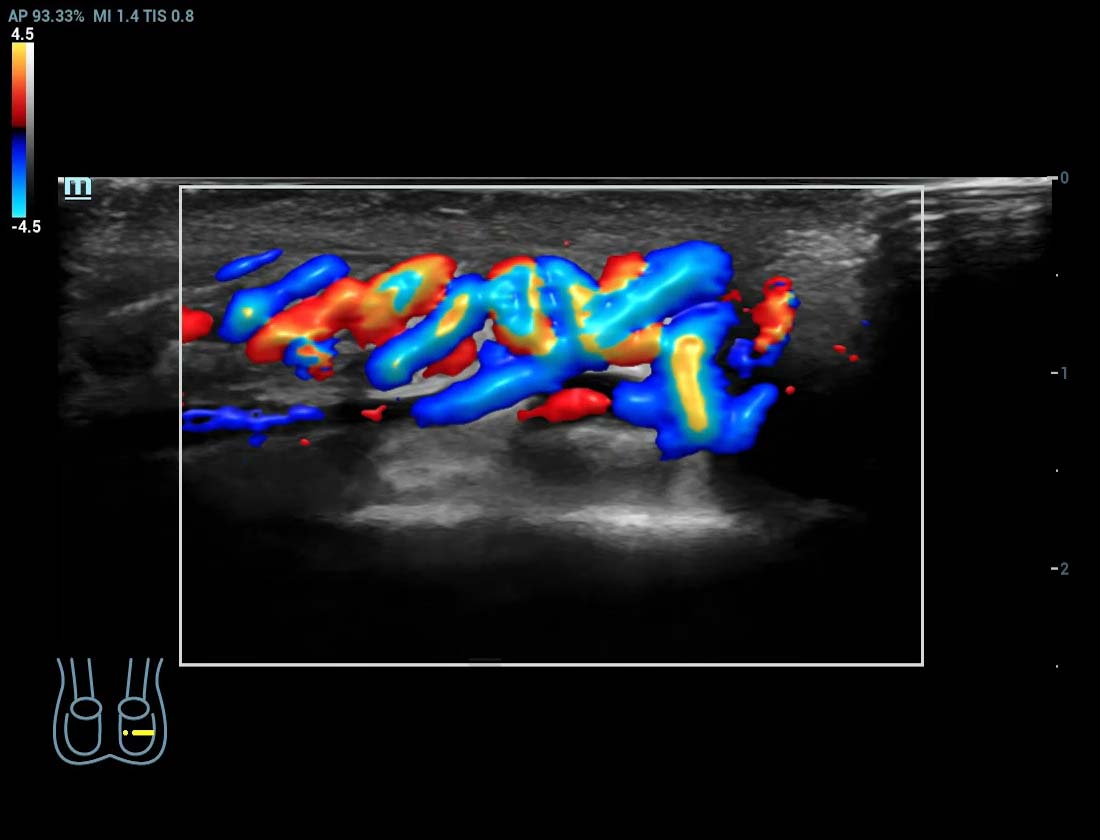

Glazing Flow em fluxo de varicocele

Angiografia ultramicroscû°pica (Ultra Micro Angiography, UMA)

UMA aumenta a confian?a diagnû°stica ao expandir a visibilidade dos fluxos sanguûÙneos atûˋ o nûÙvel de vasos minû¤sculos, com sensibilidade e resolu??o superiores.

sUMA ã Rins

pUMA ã Massa mamûÀria

sUMA ã C?ncer de tireoide

Glazing Flow sUMA em varicocele